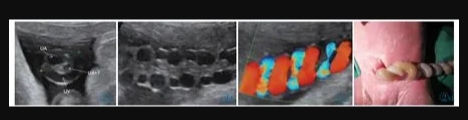

11 例中孕期超聲均可見2 條UA(膀胱水平橫切面顯示2 條UA 血流信號),超聲最后一次提示可見2 條UA 的平均孕周為(31.2±3.1)周。11 例超聲首次提示UA 數(shù)目異常(表現(xiàn)為膀胱水平橫切面UA彩色多普勒僅顯示1 條UA 及血流信號,另一側(cè)血流信號消失)的平均孕周為(36.7±2.8)周,6 例(54.4%)為膀胱左側(cè)血流信號消失,5 例(45.5%)為膀胱右側(cè)血流信號消失。7 例(63.6%)孕晚期超聲首次即提示單條UAT,這7 例臍帶游離段橫切面二維灰階圖像均顯示3 個管腔結(jié)構(gòu),其中1 條UA 內(nèi)可見稍高回聲填充且血流信號消失(圖1);1 例(9.1%)在孕34+4周提示單臍動脈,在孕37 周超聲隨訪中糾正診斷為單條UAT,因超聲提示臍帶高度螺旋,且在臍帶橫切面下見臍靜脈呈“C 形”包繞2條UA,1 條UA 內(nèi)存在血栓回聲(圖2),該病例同時合并胎兒生長受限;3 例(27.3%)整個孕期均提示單臍動脈,回顧其既往中孕期超聲均見2 條UA,晚孕期超聲發(fā)現(xiàn)1 條UA 內(nèi)存在血栓回聲(圖3)。

圖1a 臍帶橫切面。1 條臍靜脈管腔大,內(nèi)為無回聲。2 條UA 管腔小,栓塞側(cè)內(nèi)為稍高回聲(血栓回聲),通暢側(cè)內(nèi)為無回聲。圖1b 臍帶橫切面。臍靜脈及通暢側(cè)UA 內(nèi)見方向相反的血流信號,栓塞UA內(nèi)無血流信號(箭頭所示)。圖1c 臍帶縱切面。臍靜脈內(nèi)為無回聲,栓塞UA 內(nèi)等回聲為血栓(箭頭所示)。圖1d 臍帶縱切面。臍靜脈內(nèi)可見血流信號,栓塞UA 內(nèi)無血流信號。圖1e 通暢側(cè)UA:舒張末期血流流速增加,S/D 和PI 偏低。圖1f MCA:舒張末期血流流速增加,PI 值降低。Figure 1a.Cross section of cord.No echo is shown in the lumen of umbilical vein(the larger one).Two UAs have smaller lumens,and hyperecho is found in the occluded UA(thrombus).Figure 1b.Cross section of cord.Opposite blood flows are shown in umbilical vein and the normal UA,and no blood flow signal is shown in the occluded UA(as indicated by the arrow).Figure 1c.Longitudinal section of cord.There is no echo in umbilical vein and the arrow indicates the thrombus in the occluded UA.Figure 1d.Longitudinal section of cord.There is blood flow in umbilical vein and no blood flow in the occluded UA.Figure 1e.The unobstructed UA: the end diastolic blood flow velocity increases;S/D and PI decreases.Figure 1f.MCA: the end diastolic blood flow velocity increases;PI decreases.

圖2 a 臍帶橫切面。臍靜脈呈“C 形”包繞2 條UA,1 條UA 內(nèi)存在血栓回聲(T:血栓)。圖2b~2d 臍帶高度螺旋。Figure 2 a.Cross section of umbilical cord.One clogged UA is in parallel with the other unobstructed one and both of them are surrounded by umbilical vein(T: thrombi).Figure 2b~2d.Hyper-coiling of umbilical cord.